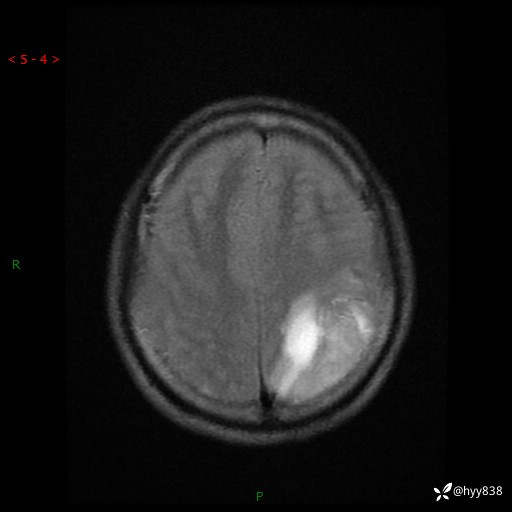

病例年轻小伙,头痛伴呕吐半年,渐进性加重1月。疑难病例,第一次见--结果公布~

性别:男

年龄:21岁

简要病史:头痛伴呕吐半年,渐进性加重1月

颅脑MRI平扫+增强